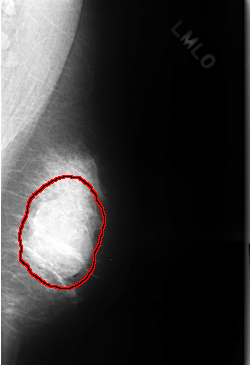

FILE: C_0324_1.LEFT_MLO.OVERLAY

TOTAL_ABNORMALITIES 1

ABNORMALITY 1

LESION_TYPE MASS SHAPE OVAL MARGINS OBSCURED

ASSESSMENT 3

SUBTLETY 4

PATHOLOGY BENIGN

TOTAL_OUTLINES 1

BOUNDARY